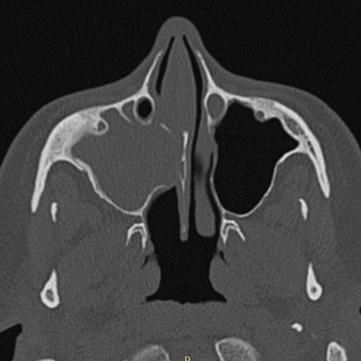

Características de Imagens

De forma geral, a sinusite odontogênica demonstra, em imagens de tomografia computadorizada, obliteração parcial ou total do seio maxilar afetado, além de espessamento da mucosa sinusal, nível líquido (sugestivo de infecção ativa), destruição ou erosão óssea do assoalho sinusal (sinal de origem odontogênica), lesão periapical associada a um dente posterior (principal achado diagnóstico), comunicação oroantral em casos de perfuração do seio, e até mesmo corpos estranhos, em casos de procedimentos odontológicos.